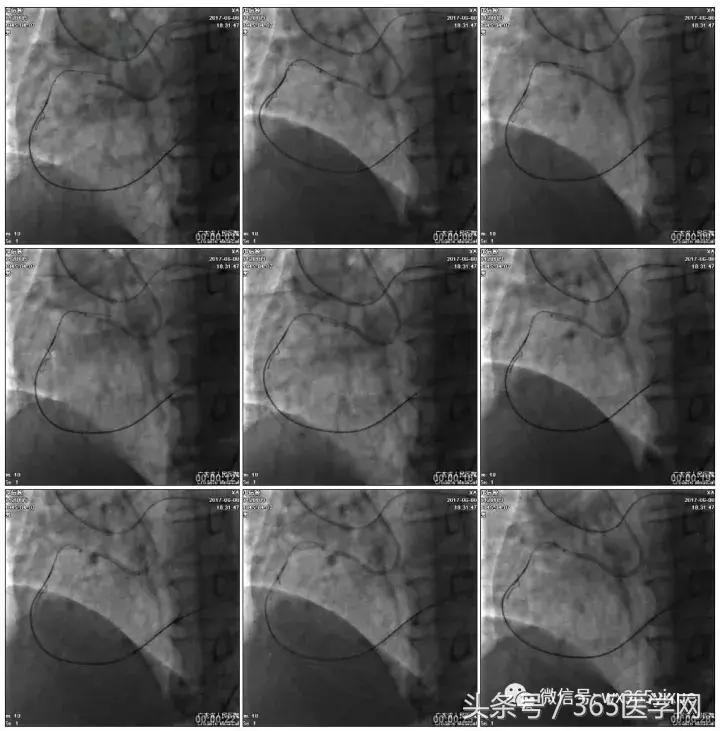

1.正向2.5*15mm球囊扩张,Reverse CART

2.Guidezilla延长导管辅助下,逆向导丝进入正向GC

1.更换RG3导丝

2.GC送入普通导丝,保护LM

RCA闭塞段球囊扩张后IVUS

支架术后造影结果

支架术后IVUS